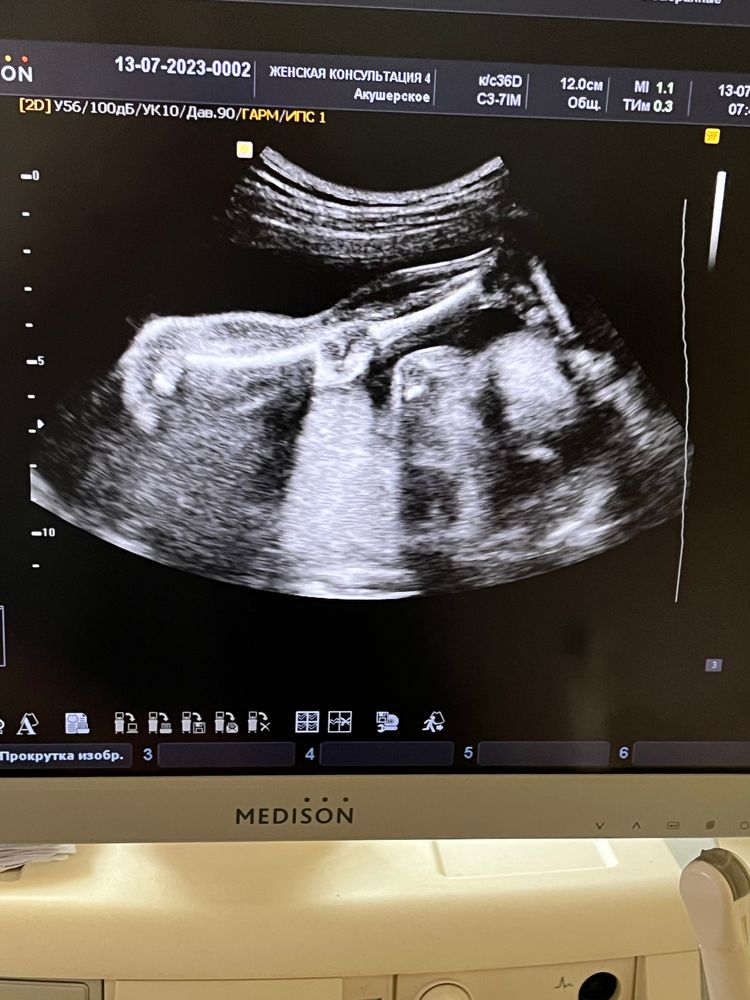

22 недели и 3 дня 🌸

Привет всем ! 30 июня был скрининг и отмены утрожестана , на всякий случай решила сходить на узи посмотреть как шейка и малыш

30.06 вес 402 грамма 27 см

13.07 вес 530 грамм 29 см 😆

а так фото с узи и вот такие мы акробаты 😂